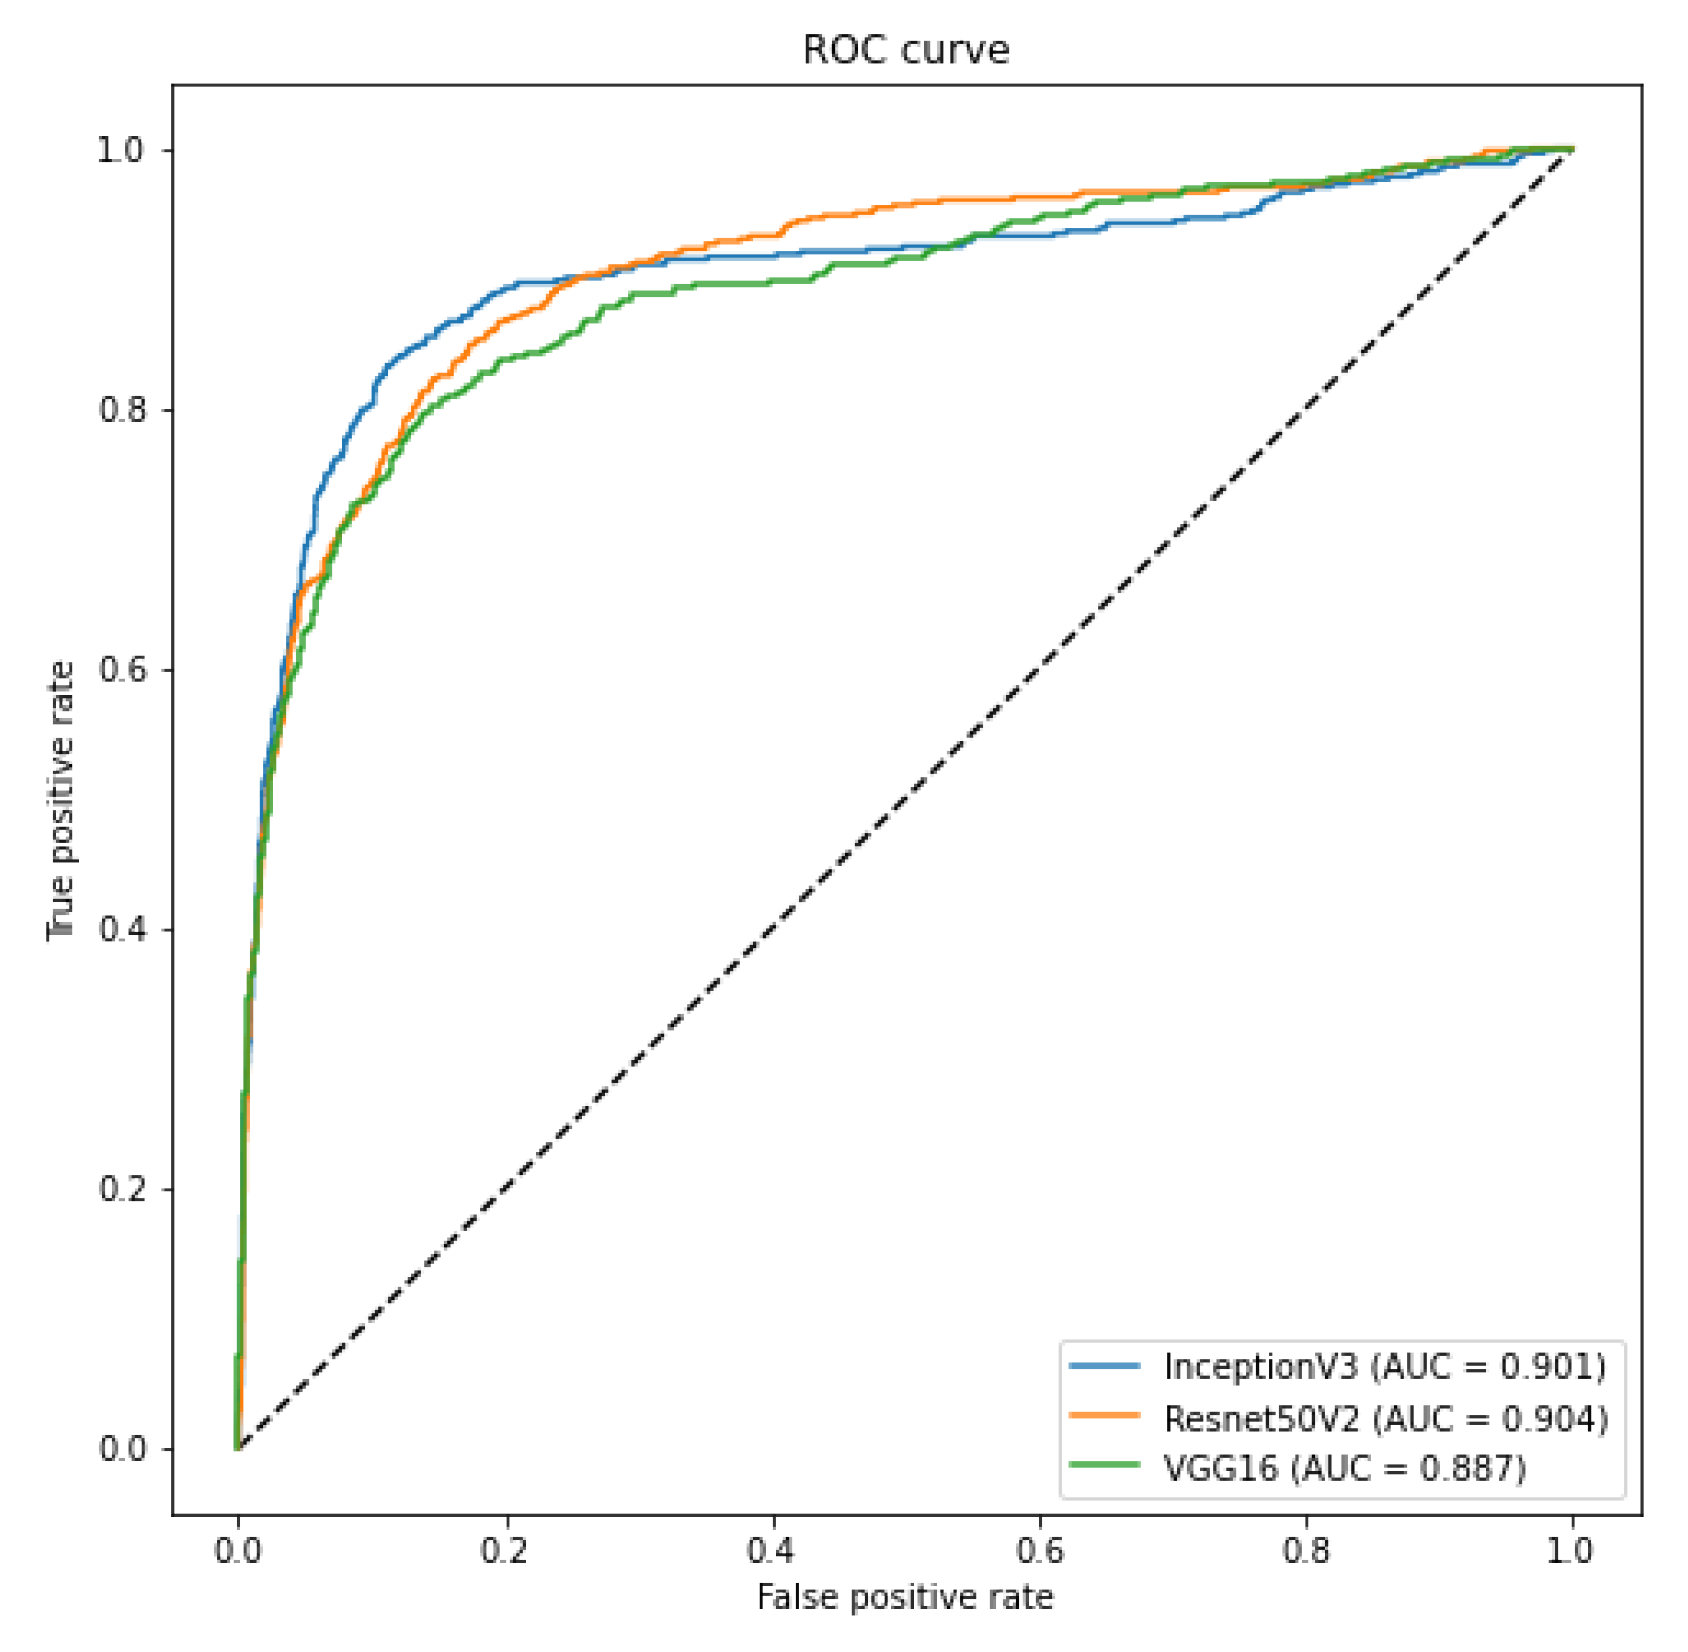

In order to evaluate such bias and provide a more realistic result, we crafted two specific scenarios to ensure that our classification model is not classifying the database source. First, as we have multiple sources of COVID-19 CXR images, we verified if it was possible to use CXR images from one database to train a model to recognize COVID-19 CXR in the other databases. We achieved a macro-averaged F1-Score of 0.74 using InceptionV3 and an area under the ROC curve of 0.9 using InceptionV3 and ResNet50V2. The F1-Score was lower than in our multi-class scenario. However, this corroborates that it is possible to identify COVID-19 cases across databases, i.e., our classification model is indeed identifying COVID-19 and not the database source. Such a scenario constitutes one of our main result and contribution, since it represents a less biased and more realistic performance, given the hurdles that still exist with COVID-19 CXR databases.